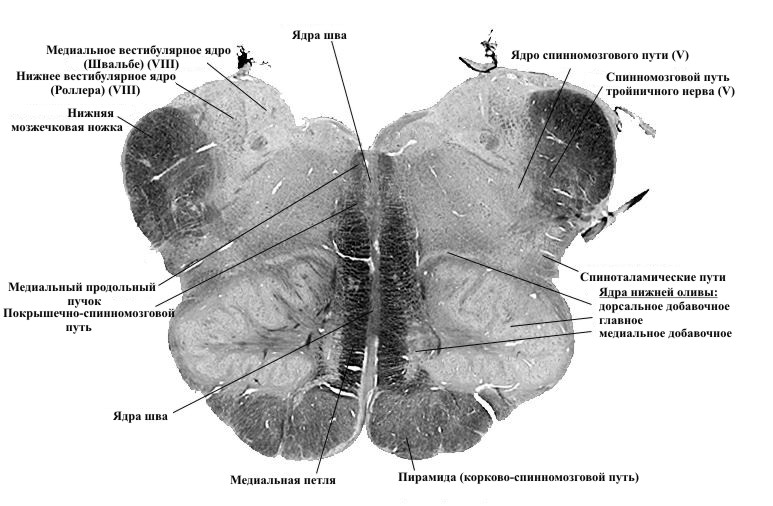

Научные исследования: Деформированные ядра и их свойства

Раздел: Визуальные истории